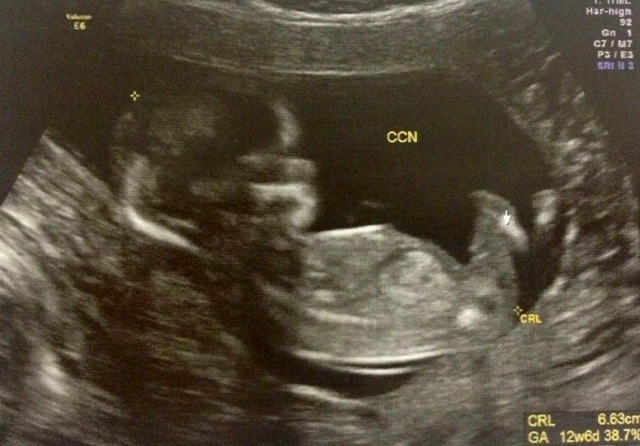

Ultrassom primeiro trimestre

Essa foto é do meu ultrassom do primeiro trimestre. Fiquei super ansiosa para fazer. O médico me explicou que com esse exame é possível detectar se o bebê foi formado perfeitamente. E para nossa alegria ele passou com louvor.

O exame é um pouco demorado, além de confirmar o sexo e ouvir o coraçãozinho (essa parte eu adoro!), são medidas todas as partes do bebê para ver se estão de acordo com a normalidade. Vimos também os rins, os órgãos formados. E, ao final, ganhamos um CD para guardarmos. Dá vontade de ter uma máquina só para ficar vendo o bebê todos os dias em casa.

Soube que agora só devemos fazer um novo ultra no próximo trimestre. Até lá vou morrer de ansiedade.